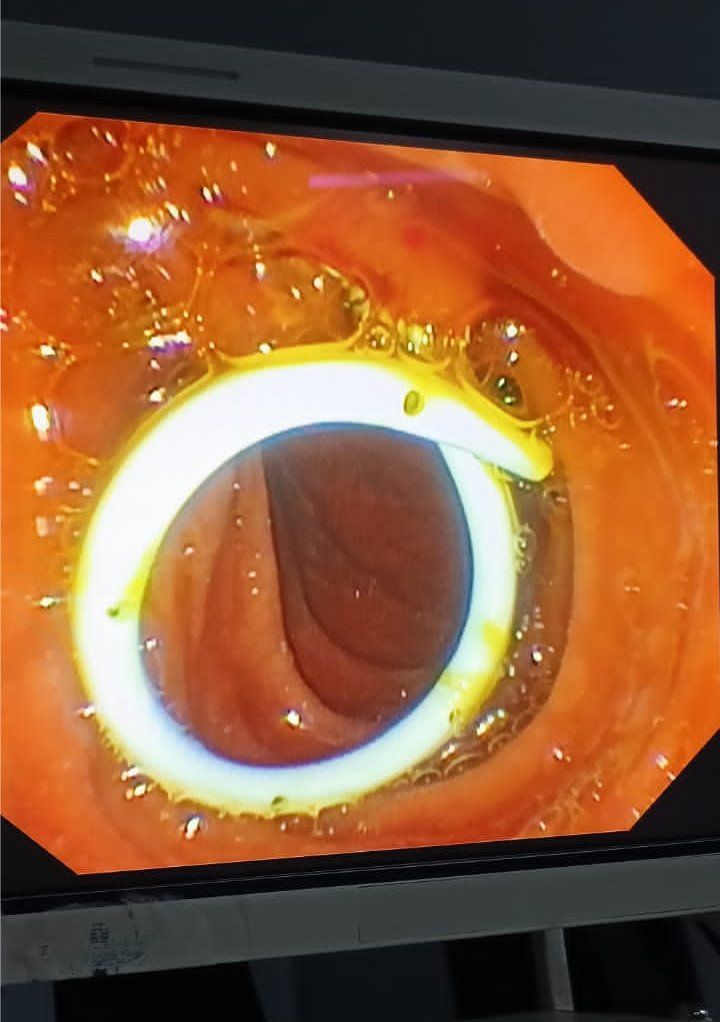

ERCP with pancreatic duct stent placement for chronic pancreatitis patients

20 year young man is a known case of early idiopathic chronic pancreatitis. The patient was admitted with complaints of recurrent upper abdominal pain radiating to the back, with inability to gain weight. Patient underwent ERCP. Pancreato-gram taken suggested dilated PD throughout the head and body, with multiple intraductal pancreatic stones. Balloon sweeps were taken with removal of multiple small white, shiny pancreatic stones. 7 Fr x 10 cm pancreatic stent was inserted. Post procedure there was a significant improvement in the patient’s quality of life with no recurrent pain episodes and weight gain.

Conclusion:

ERCP with PD stenting can improve symptoms in the select group of patients with chronic pancreatitis.